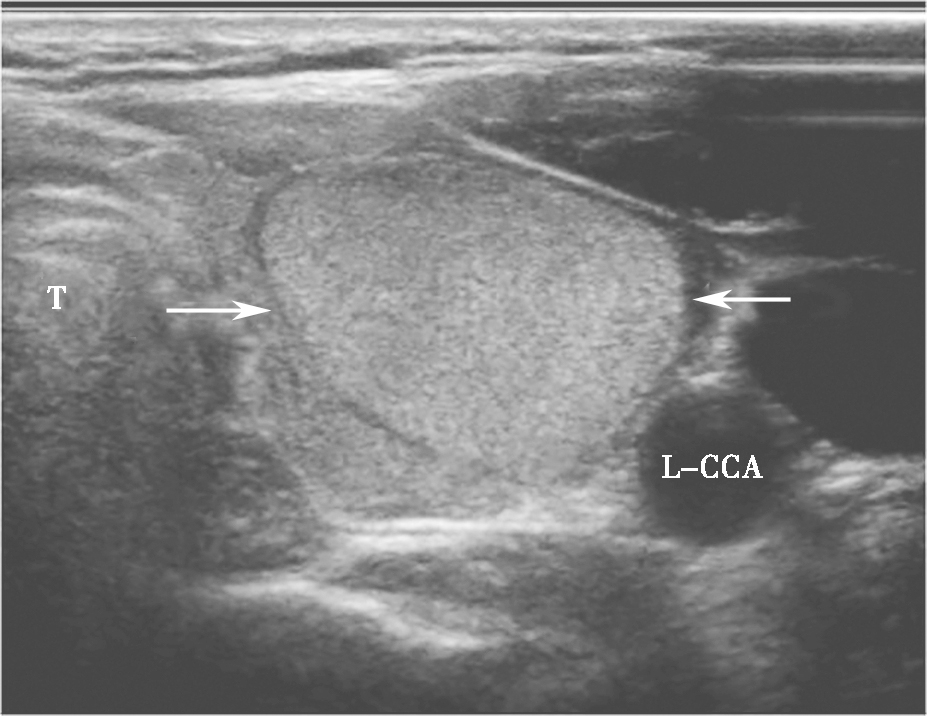

甲状腺腺瘤超声上表现为圆形或椭圆形中等回声或低回声,多伴薄声晕,肿物长轴常与腺体的长轴平行,较大者易合并囊性变、出血或坏死,内可有不规则无回声区、钙化灶或浓缩胶质,浓缩胶质表现为点状强回声后方伴“彗星尾”征,此为良性结节的特征性表现。多数腺瘤内部可见丰富规则的血流信号,周边常见较为完整的环绕血管(图7、图8)。

。T:气管;L-CCA:左侧颈总动脉.jpg)

图7颈部正中偏左横切面:甲状腺左叶中等回声,形态规则、边界清晰,伴薄声晕(箭头所示)。T:气管;L-CCA:左侧颈总动脉